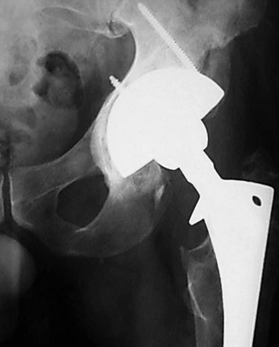

Figure 106.17. Paprosky Femoral Defect Classification. A:

Type 1 defect minimal damage able to support any type of prosthesis. Type 2 defect metaphyseal damage unable to support a proximal porous-coated device. Treat with bypass fixation or possible cemented revision in the elderly. B: Type 3A defect extensive proximal femoral damage diaphyseal fixation is available proximal to the isthmus. Type 3B defect has damage that extends even further and diaphyseal fixation is available only past the isthmus. What appears to be a radiographic type 3B may not be able to support a prosthesis intraoperatively and must then be treated as a type 4. C: Type 4 defect has extensive diaphyseal involvement. It is unable to provide rotational and axial stability to a fully porous-coated device and is treated with impaction grafting or an allograft prosthetic composite. |

of the femoral diaphysis to support an uncemented, fully porous-coated

prosthesis (3) (Fig. 106.17).

This system is less detailed in its description of the bony defect

present than the AAOS system, yet it is more useful in decision making

for an uncemented femoral revision. By using this classification

system, the appropriate method of treatment can be chosen

preoperatively (Table 106.8).